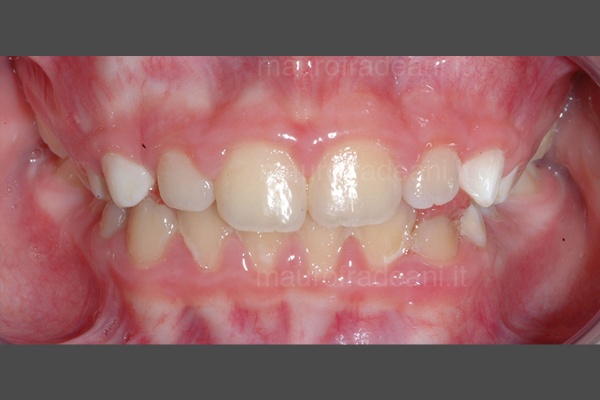

Early orthodontics: malocclusion and tooth crowding

1/6: Initial picture taken before early orthodontic treatment. The young patient presents a first class malocclusion with misalignment and dental crowding in both arches. The upper right central incisor is in reverse bite with the lower one.

2/6: Upper occlusal picture showing the misalignment of the upper central incisors.

3/6: Lower occlusal picture showing the dental crowding on the lower arch.

4/6: The right lateral view shows the backward position of the upper right central incisor, which determines the incorrect occlusion with the lower arch.